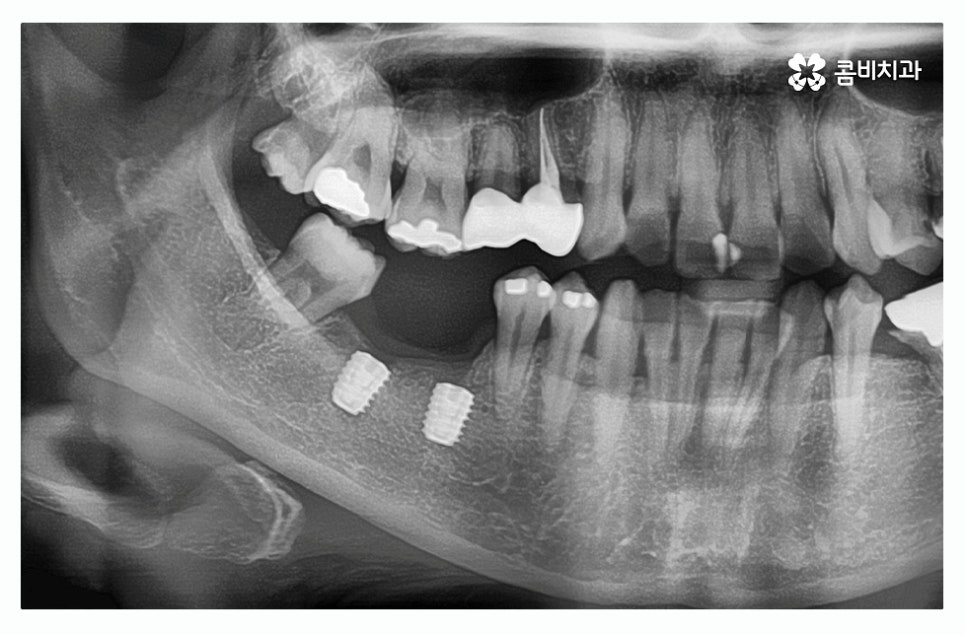

치주염이 심해져서 치아를 상실하게 되는 경우에는 치아를

한꺼번에 여러 개 잃게 되는 경우도 많기 때문에

임플란트를 하나만 식립하는 것이 아니라 여러 개 식립을

하는 경우가 있겠고 임플란트는 잇몸 뼈에 식립을

하기 때문에 치주질환이 심했던 경우 잇몸 뼈가 부족해서

뼈이식 임플란트나 상악동 거상술을 해야 하는 경우도 있어요.

임플란트를 진행할 때 치조골에 치아의 뿌리 역할을 하는

인공 치근을 식립하고 잇몸 뼈와 골 유착이 튼튼하게

되도록 하는 과정을 거치게 되는데 뿌리 역할을 하는 만큼

잇몸의 상태가 건강해야 하고 뼈가 충분히 있어야

건강하게 치료를 진행할 수 있어요.